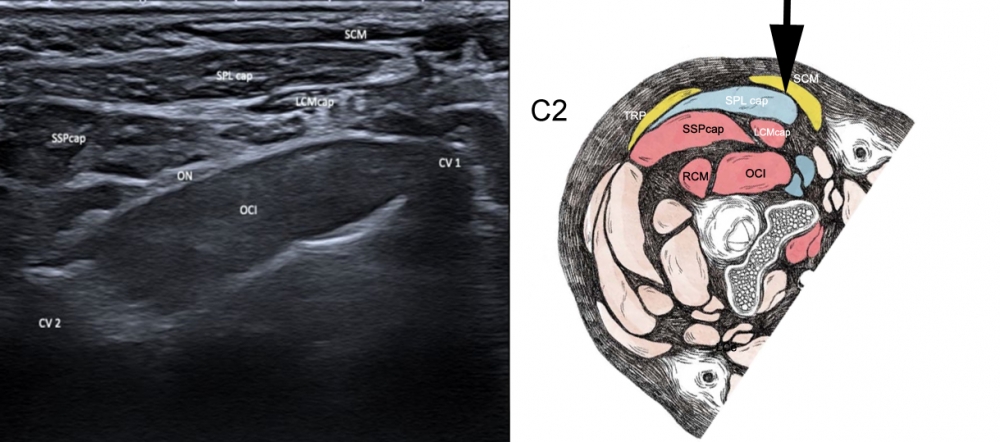

Ultrasound-Anatomical correlation

Figure 1. Ultrasound at level of C2. Approach indicated by black arrow.